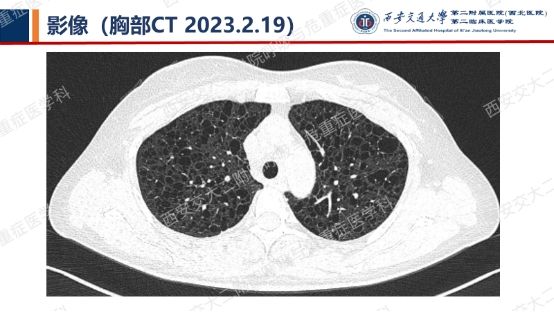

结合以上患者病史及胸部CT,第一诊断分别考虑???欲知答案,且看后期!!!